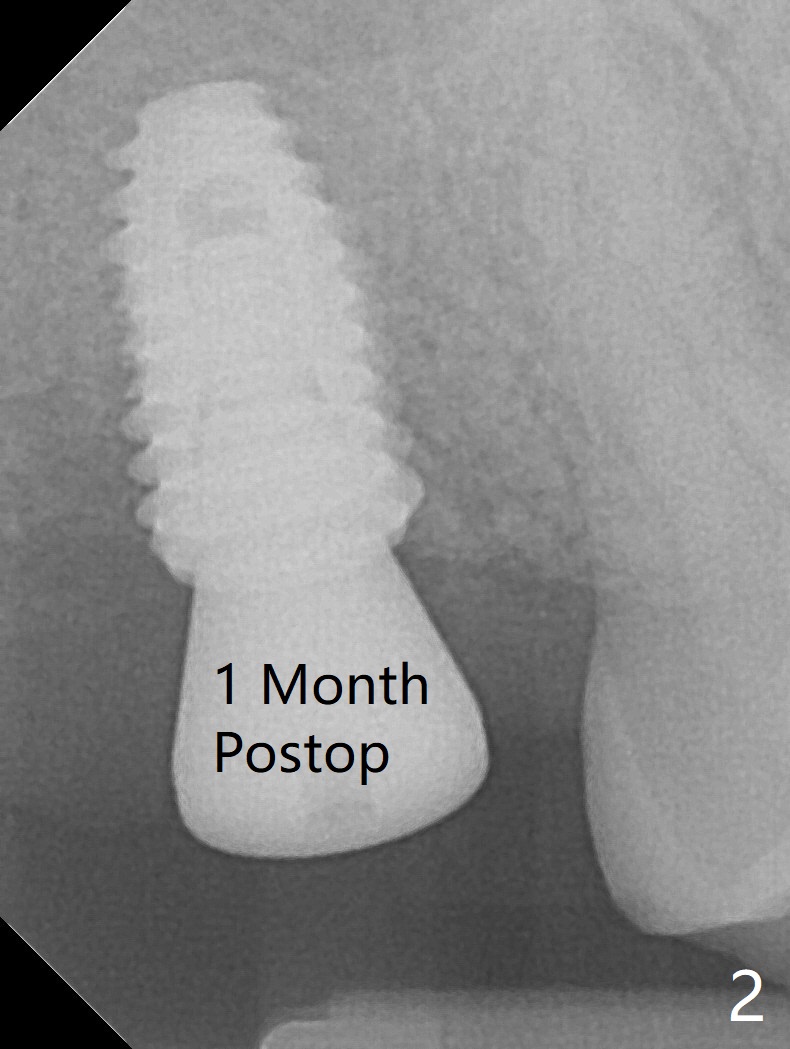

In spite of underprep (4.0x8.5 mm last drill), a 5x8.5 mm implant is placed at #2 with insertion torque ~ 15 Ncm (Fig.1). In addition to the large defect post implant removal with 4.5 month bone graft, he is a heavy gagger with limited mouth opening. Drill cylinders may not engage the metal sleeve precisely. A 5.5x4 mm healing abutment is placed with low emergency profile. The procedure, although difficult, finishes in a timely manner. Otherwise it would be a disaster for the patient and operator. PA taken 1 month postop shows slightly subcrestal placement (Fig.2). When a cemented abutment is placed 4 months postop, there is tenderness. In fact the implant is mobile. A 8x5 mm healing abutment is placed. Nine months postop, the implant remains slightly mobile (Fig.3); a healing screw is placed. The tooth #3 has sign and symptom of crack 13 months postop (Fig.4), related to root fracture of #19 (Fig.5, bruxism). In fact the tooth cracks nonsalvageable post RCT, 9 months post #2 healing screw, 21 months postop. Socket preservation will be carried out with sticky bone and PRF, while #2 implant will be uncovered, followed by placement of a short cemented abutment to hold periodontal dressing. Upper Molar Immediate Implant, Trajectory Xin Wei, DDS, PhD, MS 1st edition 11/27/2018, last revision 07/03/2021